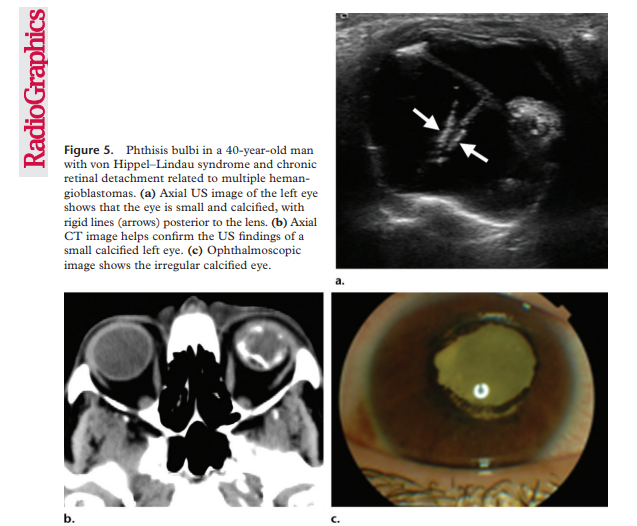

Phthisis bulbi

clinical condition representing end-stage ocular response to severe eye injury or disease damage, related to a variety of causes leading to scarring, inflammation, scaring, atrophy and eventually disorganization of the globe and intraocular contents. Also called end-stage eye, phthisis bulbi can be described as a shrunken, collapsed in form, non-functional eye and presents with a small squared off shape, opaque and thickened cornea, thickened sclera, neovascularization of iris, cataract, cyclitic membrane, ciliochoroidal detachment, and retinal detachment. A mnemonic rule used to describe phthisis bulbi is ”7S” referring to : Soft – Shrunken – Shapeless – Sightless – Structureless – Squared – Sore.